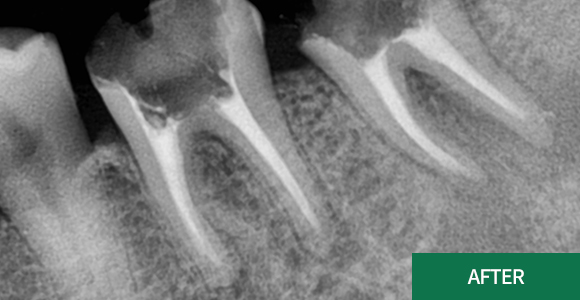

신경치료

재근관치료